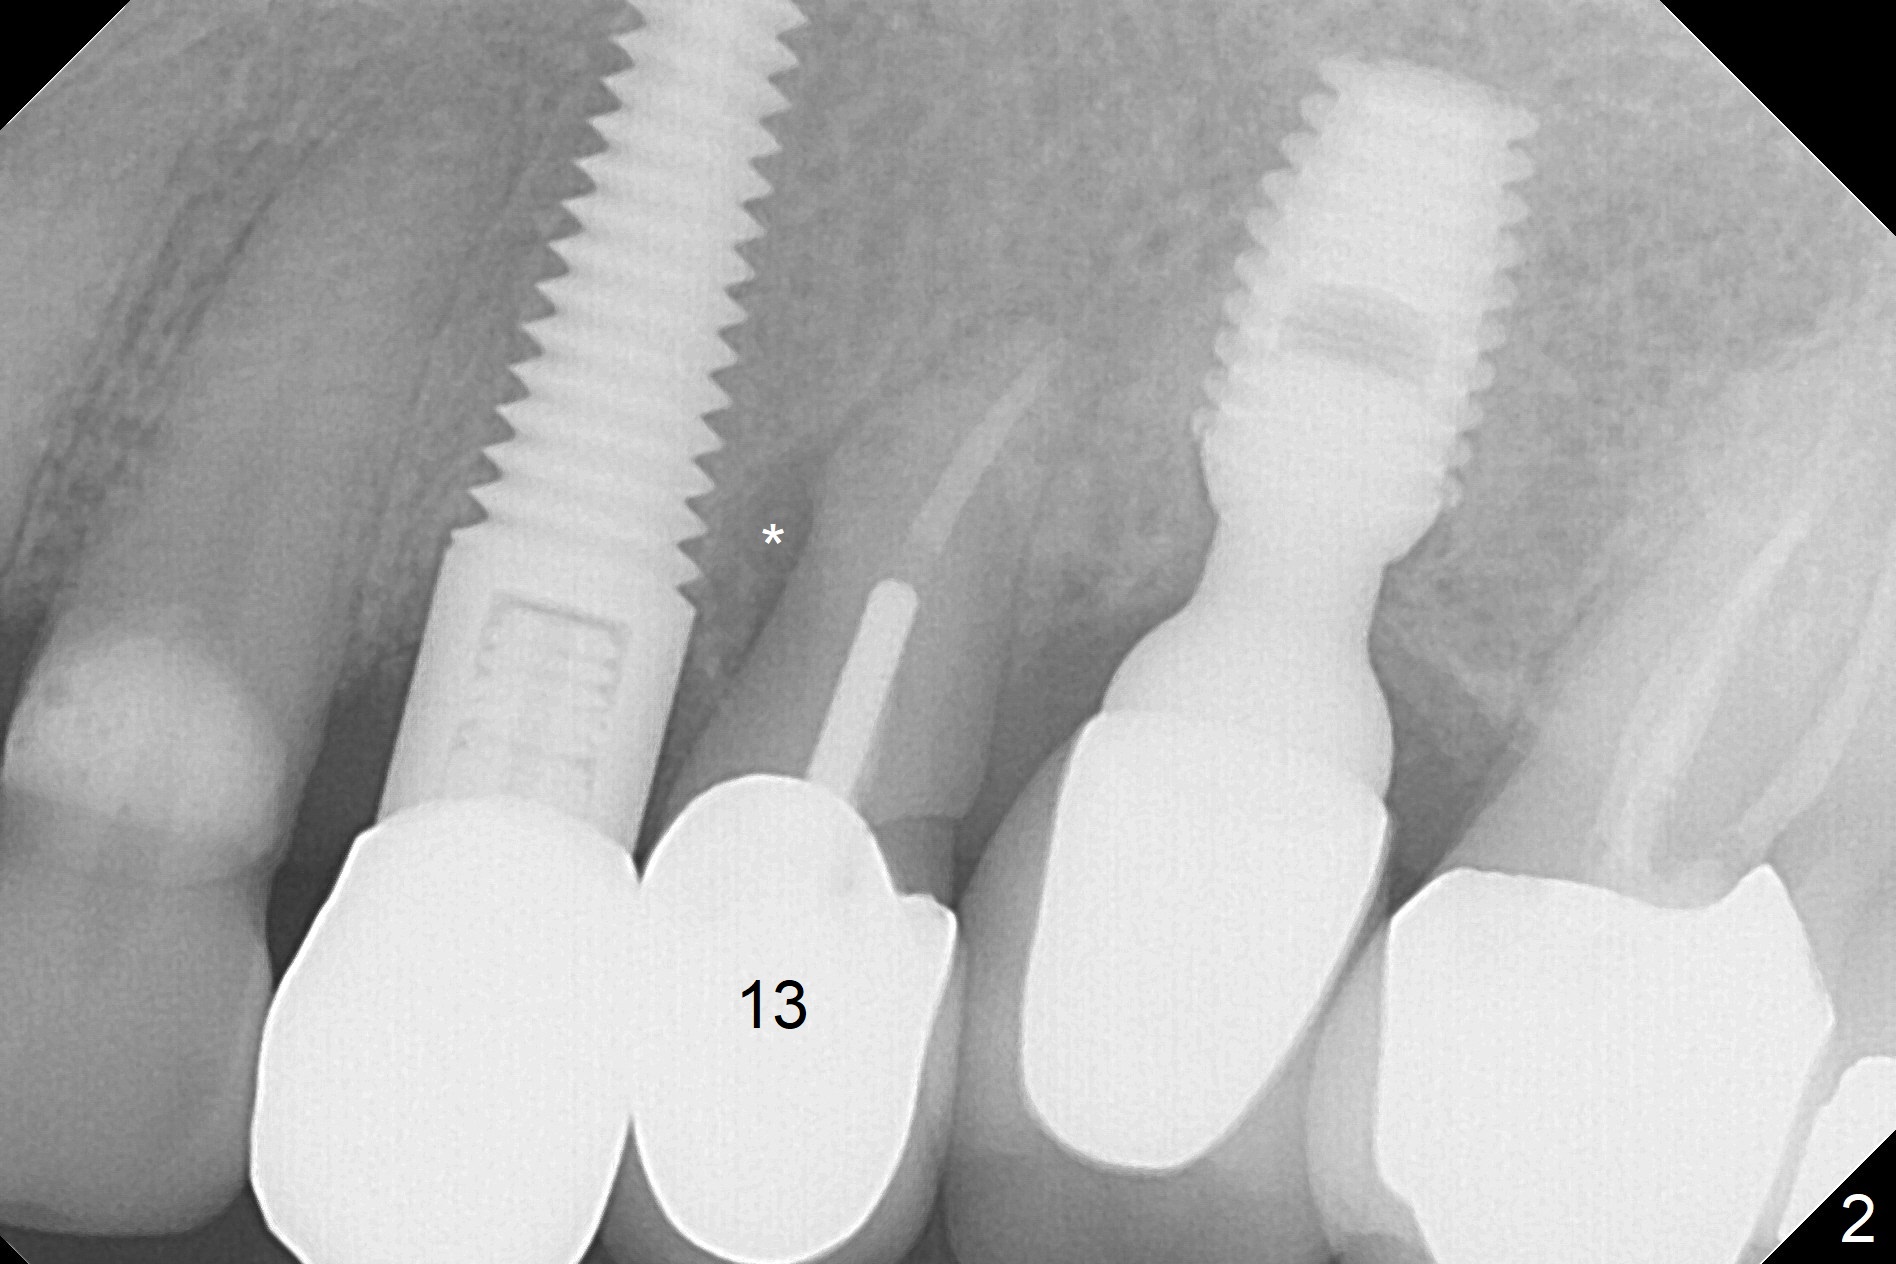

A 59-year-old woman has mild discomfort in the upper left quadrant, which is alleviated by salt water rinse. The buccal gingiva recedes at #13 with mesiobuccal swelling and deep pocket (Fig.1,3), corresponding to the mesial radiolucency (Fig.2 *). The tooth appears to have vertical fractured root, as related to the retention post. Since the root tip curves distal, the initial osteotomy (Fig.5 red) should be established in the mesioapical slope after extraction (black). Following initial entrance, the trajectory will be changed to the long axis of the space (Fig.6) with PA to be taken. Measure the depth of the buccal crest against the buccal, proximal and palatal gingival margins. Place an implant, the same as #12 (4.5x20 mm) unless the mesiobuccal defect is extremely large (UF).